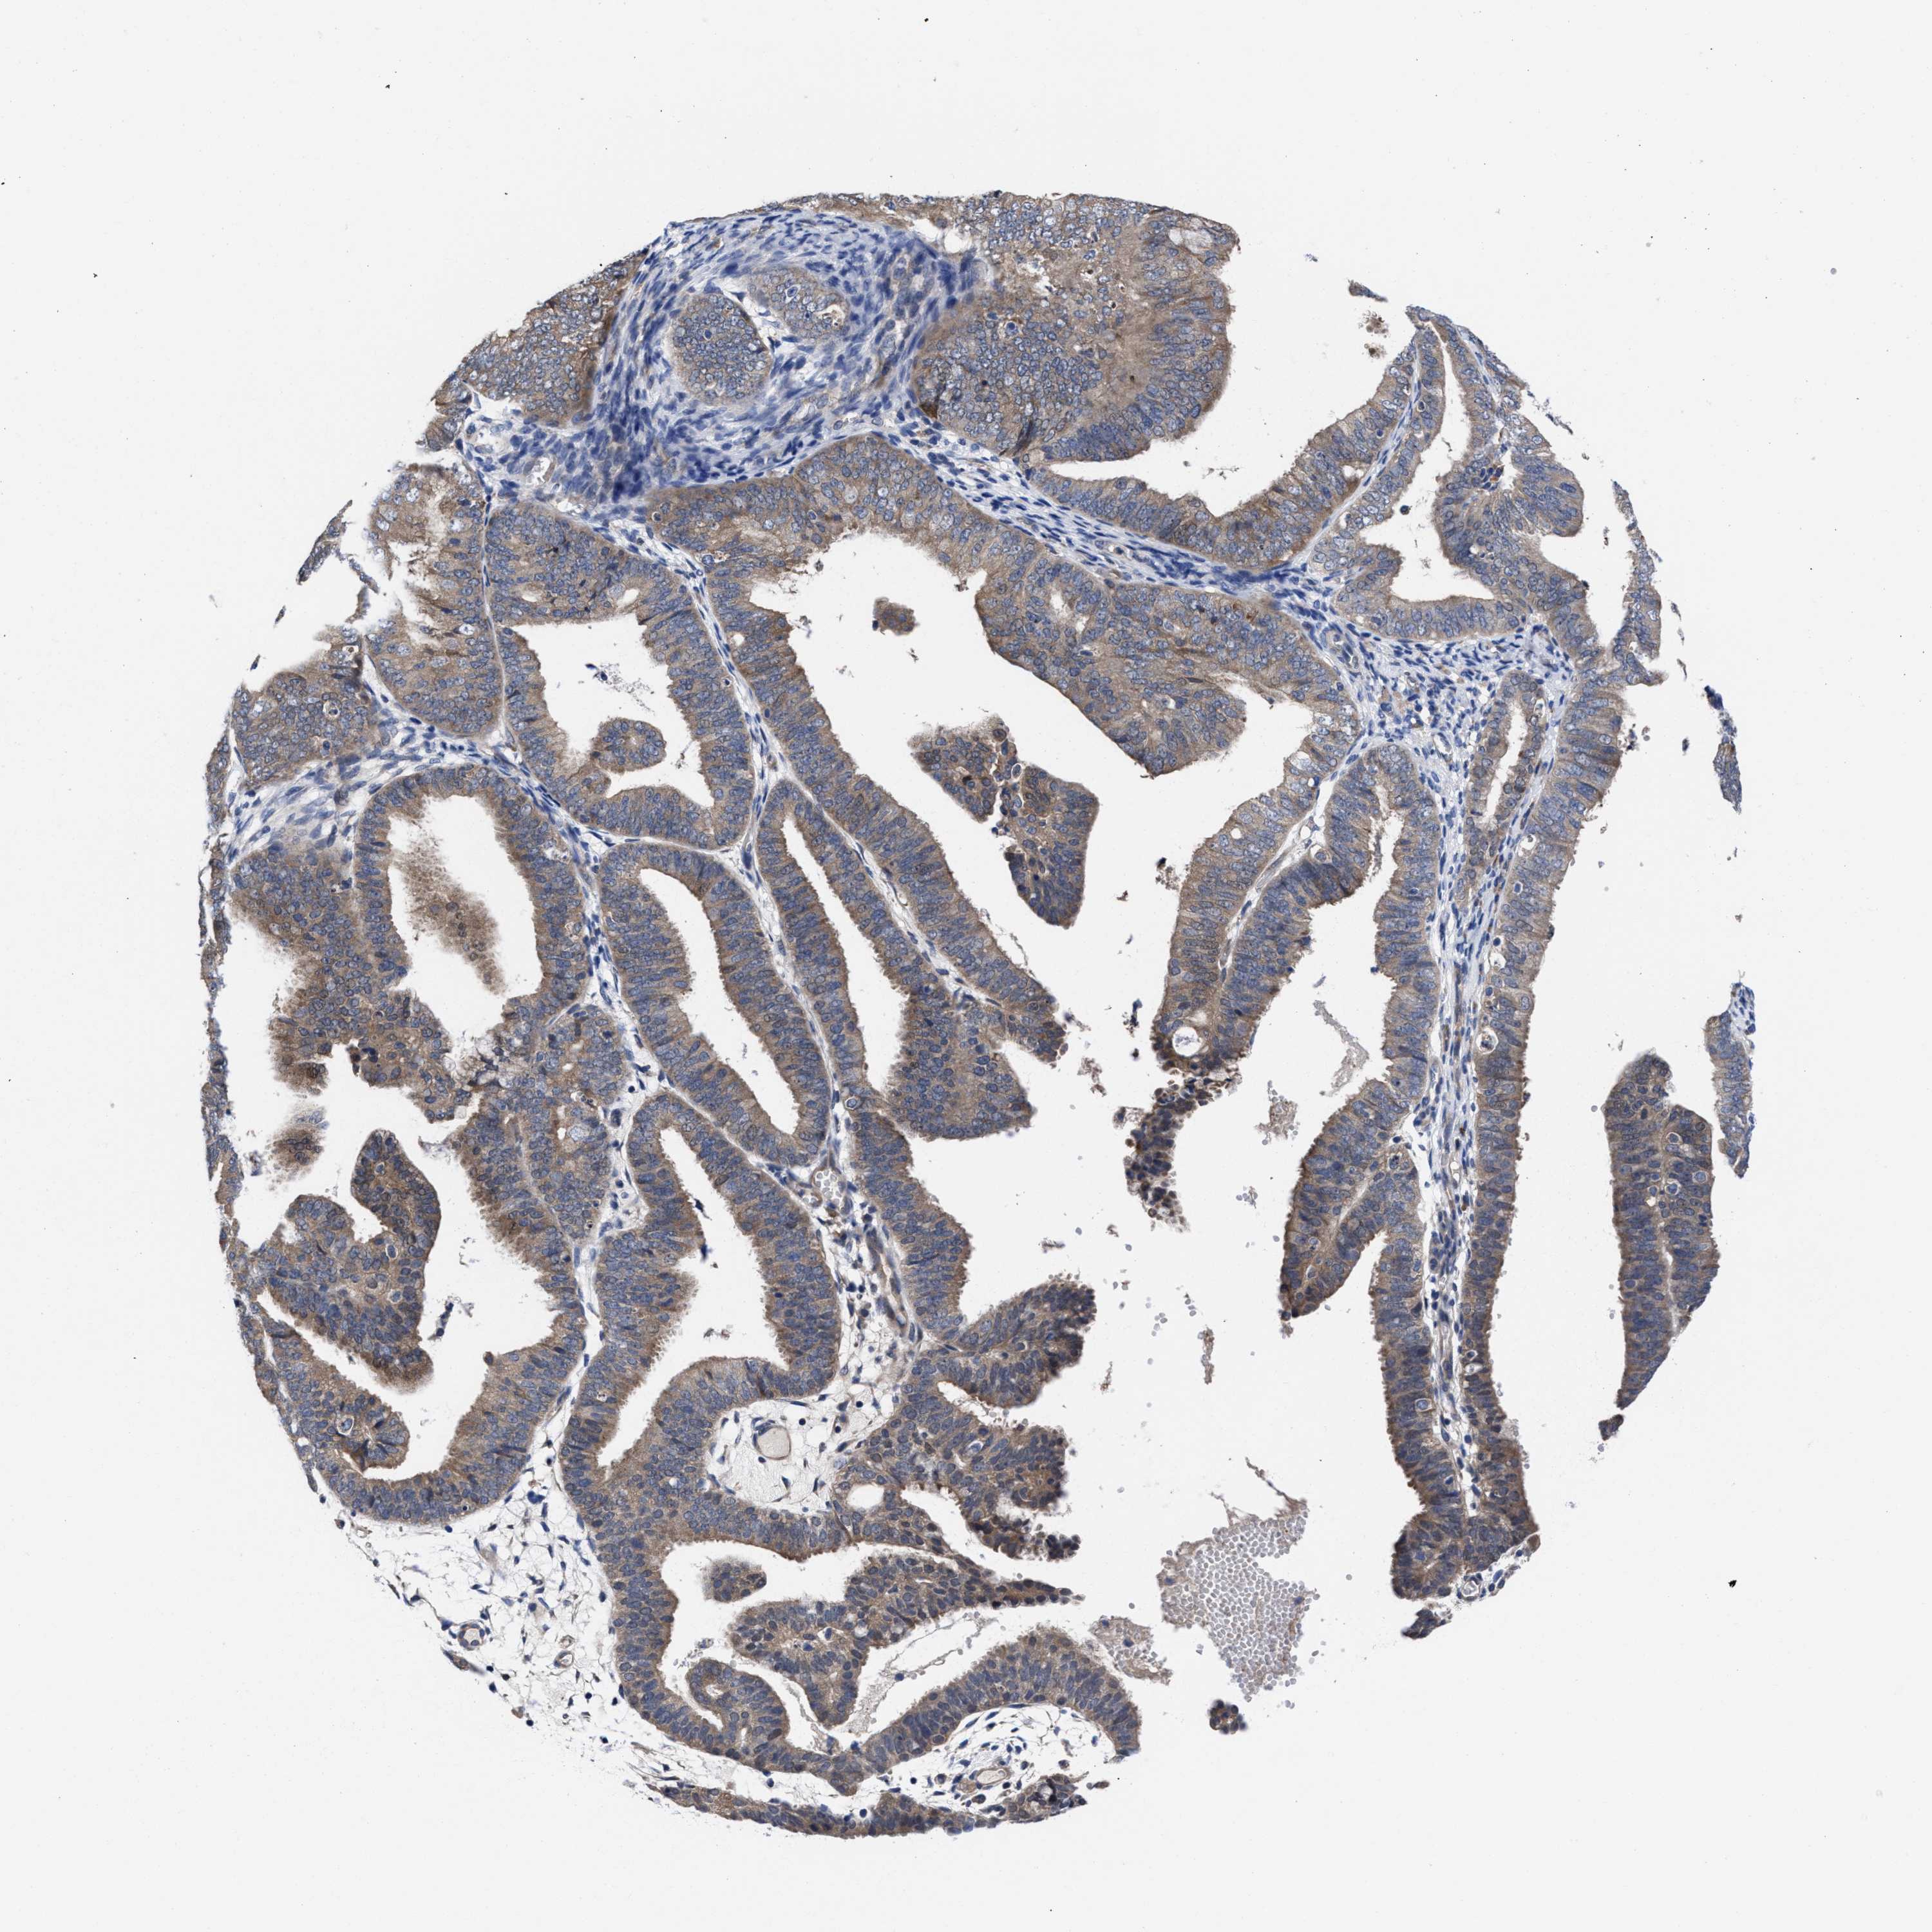

ENDOMETRIAL CANCER - Protein expressioni

A mouse-over function shows sample information and annotation data. Click on an image to view it in a full screen mode. Samples can be filtered based on level of antibody staining by selecting one or several of the following categories: high, medium, low and not detected. The assay and annotation is described here.

Note that samples used for immunohistochemistry by the Human Protein Atlas do not correspond to samples in the TCGA dataset.

Antibody stainingi

Antibody staining in the annotated cell types in the current human tissue is reported as not detected, low, medium, or high, based on conventional immunohistochemistry profiling in selected tissues. This score is based on the combination of the staining intensity and fraction of stained cells.

Each image is clickable and will lead to virtual microscopy that enables deeper exploration of all samples and also displays staining intensity scores, fraction scores and subcellular localization as well as patient and tissue information for each sample.

Antibody HPA022931

Staining

High

Medium

Low

Not detected

Intensity

Strong

Moderate

Weak

Negative

Quantity

>75%

75%-25%

<25%

None

Location

Nuclear

Cytoplasmic/membranous

Cytoplasmic/membranous,nuclear

Adenocarcinoma, NOS

Adenoma, NOS